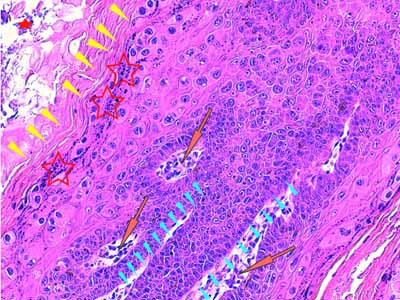

A l’examen histologique, on observe des néoformations verruqueuses, exophytiques, constituées d’un épiderme bien différencié, sévèrement hyperplasique, produisant à la surface du tégument, des projections digitées, longues et étroites (Fig 2). Cet épiderme est le siège d’une sévère hyperkératose orthokératosique ou parakératosique et d’une hypergranulose avec de volumineux grains de kératohyaline (Fig 3 &6). Sa couche basale est très développée, cellulaire, mitotique, hyperbasophile (Fig 4 & 5). Les acanthocytes sous-cornés sont vacuolisés (Fig 3 & 7). Ils montrent un cytoplasme bleuté, discrètement fibrillaire (Fig 6), ou vacuolisé, leur noyau parfois pycnotique étant entouré d’un halo clair. Il s’agit de koïlocytes (Fig 7). Certains montrent un noyau avec margination chromatinienne laissant un centre bleuté compatible avec une inclusion basophile (Fig 7). Dans le derme papillaire sous-jacent, on observe un infiltrat inflammatoire lympho-plasmocytaire d’intensité modérée. Absence d’image suspecte de malignité.

Légendes de la Photo 4 :

- Pointes de flèche jaunes : couche cornée hyperkératosique (parakératose)

- Étoiles rouges évidées : couche granuleuse hypergranuleuse abritant de nombreux et volumineux grains de kératohyaline

- Flèches oranges : derme papillaire siège d’un infiltrat lympho-plasmocytaire modéré

- Pointes de flèche turquoises : elles délimitent le contour du plancher d’une papille épidermique qui est formé d’une crête épithéliale densément peuplée de kératinocytes au noyau hyperchromatique

- Étoile rouge pleine : présence d’amas de bactéries bleutées cocciformes dans la couche cornée